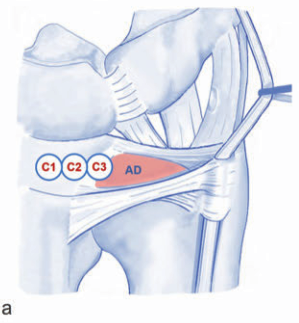

3. 2024년 논문이 밝힌 'CUP'의 마법(진단 분류)

이제 내 손목 상태를

알파벳 세 글자 C.U.P.로 확인하세요!

C (Central - 중앙):

연골판 중앙에 구멍이 난 상태입니다.

타이어 펑크처럼 완충 능력이 떨어지죠.

U (Ulnar - 척측):

가장 중요합니다!

뼈를 잡고 있어야 할

인대 뿌리가(중심와 층) 뽑힌 상태로,

손목이 매우 불안정해집니다.

P (Peripheral - 주변부):

손목 캡슐이나 주변 인대,

힘줄막이 찢어진 경우입니다.